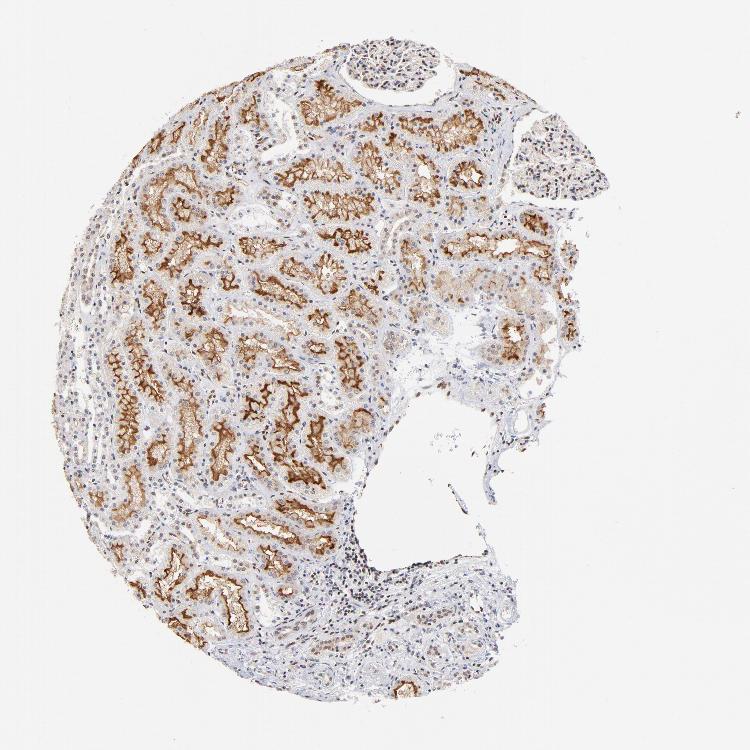

TISSUE PRIMARY DATA KIDNEY Show tissue menu

KIDNEY - Antibody stainingi

Antibody staining in the annotated cell types in the current human tissue is reported as not detected, low, medium, or high, based on conventional immunohistochemistry profiling in selected tissues. This score is based on the combination of the staining intensity and fraction of stained cells.

Each image is clickable and will lead to virtual microscopy that enables deeper exploration of all samples and also displays staining intensity scores, fraction scores and subcellular localization as well as patient and tissue information for each sample.

Antibody HPA003258Antibody HPA028791Antibody CAB004411

Cells in glomeruli LowMediumLow

Cells in tubules LowMediumLow